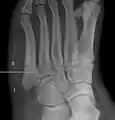

![]() | |

| Jones fracture as seen on Xray | |

The fracture typically occurs when the toes are pointed and the foot bends inwards.[6][2] This movement may occur when changing direction while the heel is off the ground such in dancing, tennis, or basketball.[9][10] Diagnosis is generally suspected based on symptoms and confirmed with X-rays.[3]

Diagnostic x-rays include anteroposterior, oblique, and lateral views and should be made with the foot in full flexion.